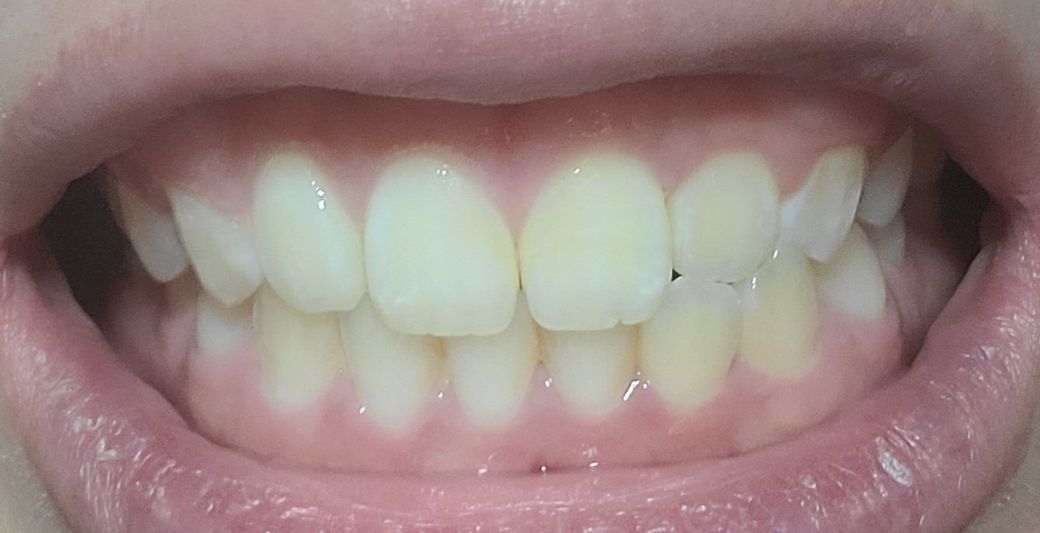

정면

제일 위 첫번째 사진에서 윗니 1개(측절치)가 아랫니(측절치) 보다 안쪽으로 들어가 있어 정상 치아 교합이 아닙니다

왼쪽이 제1소구치쪽부터 교합이 아주 이상적인 교합은 아닙니다. 또한, 오른쪽 2번째 치아는 원래 위 치아가 아래치아를 덮어야하는데, 그렇지 않고 치아끼리 바로 닿습니다. 이 경우 치아에 무리가 갈 수 있습니다.

치아는 상악치아가 하악 치아보다 앞으로 살짝 나와있기 때문에 치아를 덮으면서 빈공간이 없어보이게 됩니다.

하지만 사진과 같이 오른쪽 2번째 윗니와 아랫니가 절단교합이 되어 있으면 치아가 다 내려오지 않아서 공간이 보일수 있어요.